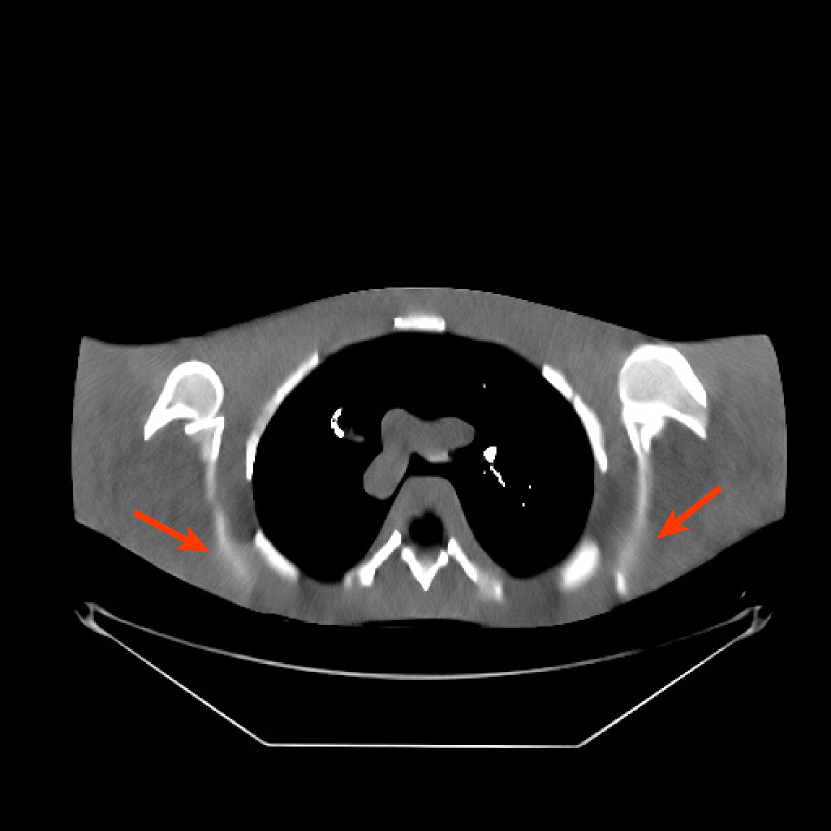

Fig. 9 shows three axial slices from the 3D reconstructions with SPULTRA and PWLS-ULTRA at : the middle slice (No. 67) and two slices located farther away from the center (No. 90 and No. 120). The image profiles along a horizontal line (shown in green) in the displayed slices are also shown in Fig. 9. The reconstructed slices using PWLS-ULTRA appear darker around the center compared to the “true” clinical image and the reconstructions with SPULTRA. This means PWLS-ULTRA produces a strong bias in the reconstruction. The bias can be observed more clearly in the profile plots: the pixel intensities for the SPULTRA reconstruction better follow those of the “true” clinical image, while those for the PWLS-ULTRA reconstruction are much worse than the “true” values. Moreover, SPULTRA achieves sharper rising and failing edges compared to PWLS-ULTRA. In other words, SPULTRA also achieves better resolution than PWLS-ULTRA. Fig. 9 also shows a zoomed-in ROI for each of the chosen slices, and highlights some small details with arrows. It is clear that in addition to reducing the bias, SPULTRA reconstructs image details better than PWLS-ULTRA.